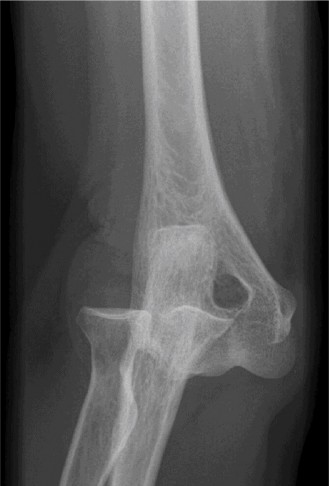

It should be noted that reverse total shoulder arthroplasty is also the procedure of choice in patients with cuff-tear arthropathy (aka rotator cuff arthropathy). Characteristics of cuff-tear arthropathy include superior migration of the humerus due to a massive rotator cuff tear, glenohumeral joint destruction, subchondral osteoporosis, and humeral head collapse (see Fig. 2–17). A reverse total shoulder

Figure 2–17_X-rays of a patient showing evidence of cuff tear arthropathy. The humerus is migrated superiorly, the glenohumeral joint is destroyed, there is subchondral osteoporosis, and the humeral head is collapsed. (From Ecklund KJ, Lee TQ, Tibone J, Gupta R. Rotator cuff tear arthropathy. _J Am Acad Orthop Surg. 2007;15(6):340–349.)